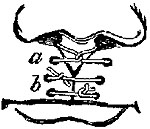

The four plates which precede the letterpress were drawn on wood (from original photographs) by Mr. D.W. Williamson, Melbourne Place, and the lines of incision for the various operations were added by the author.

The rough woodcuts scattered through the work were drawn on wood by the author, and for their roughness he, not his engraver, is responsible. He also hopes that the references in the letterpress will be accepted as sufficient acknowledgment of the true ownership, in those few instances in which the idea of the diagram has been borrowed.